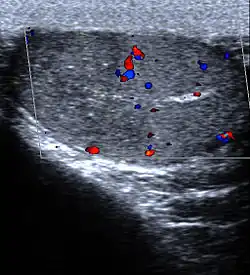

Limb: Limb infarction is an infarction of an arm or leg. Causes include arterial embolisms and skeletal muscle infarction as a rare complication of long standing, poorly controlled diabetes mellitus.[11] A major presentation is painful thigh or leg swelling.[11]